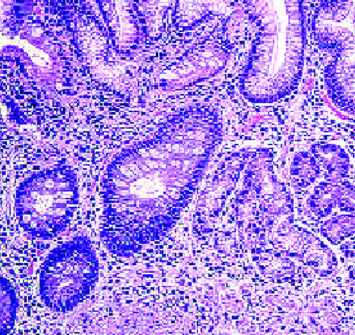

behet病(BD)是一种引起口腔溃疡、生殖器溃疡、眼睛炎症和皮肤病变的全身性炎症。自身炎症和自身免疫性疾病是导致组织炎症的慢性免疫系统激活。目前的证据表明,双相障碍是自身免疫综合征和自身炎症综合征的交叉点,一些研究结果表明其具有自身炎症的性质。口腔溃疡是该疾病最常见的初始表现。胃症状在BD中并不常见。胃溃疡或胃炎通常表现为胃脘痛。双相障碍与几种自身免疫性疾病有关;然而,在自身免疫性萎缩性胃炎中尚未发现。我们报告一位62岁男性病患,以口腔阿弗顿溃疡为主诉,并伴有腹痛、上腹部不适及餐后恶心。患者HLA-B5等位基因呈阳性,诊断为BD。胃镜和结肠镜检查了该患者胃脘不适和腹痛的可能病因。胃镜检查显示眼底多处糜烂,胃体处有萎缩褶皱,结肠镜检查未见重要发现。此外,胃活检证实在胃底和胃窦水平存在自身免疫性萎缩性胃炎,这在BD中是不典型的,通常与回肠末端水平的阿佛氏溃疡有关。据我们所知,这是第一例报道,这应该促使我们进一步调查这两种疾病之间的联系机制。

Behçet's disease (BD) is a systemic inflammatory condition causing oral ulcers, genital sores, eye inflammation, and skin lesions. Autoinflammatory and autoimmune disorders are chronic immune system activation leading to tissue inflammation. Current evidence suggests that BD is at the intersection of autoimmune and autoinflammatory syndromes, with some findings suggesting an autoinflammatory nature. Oral aphthous ulcers are the commonest initial manifestation of the disease. Gastric manifestations in BD are infrequent. The usually seen finding in the stomach is either ulcers or gastritis, presenting as epigastric pain. BD has been linked with several autoimmune diseases; however, it has not yet been seen with autoimmune atrophic gastritis. We present a case of a 62-years-old male patient presenting for oral aphthous ulcers with vague abdominal pain, epigastric discomfort, and postprandial nausea. The patient was positive for HLA-B5 alleles, leading to a diagnosis of BD. Gastroscopy and colonoscopy were done to investigate a probable etiology for this patient's epigastric discomfort and abdominal pain. Gastroscopy showed multiple erosions at the level of the fundus and atrophic folds at the level of the body of the stomach, but no important findings were seen on colonoscopy. Furthermore, a gastric biopsy was done and confirmed the presence of autoimmune atrophic gastritis at the level of the fundus and antrum of the stomach which is atypical in BD that is commonly associated with aphthous ulcerations at the level of the terminal ileum. To our knowledge, this is the first case reported, which should prompt for further investigation behind the mechanism linking these two diseases.